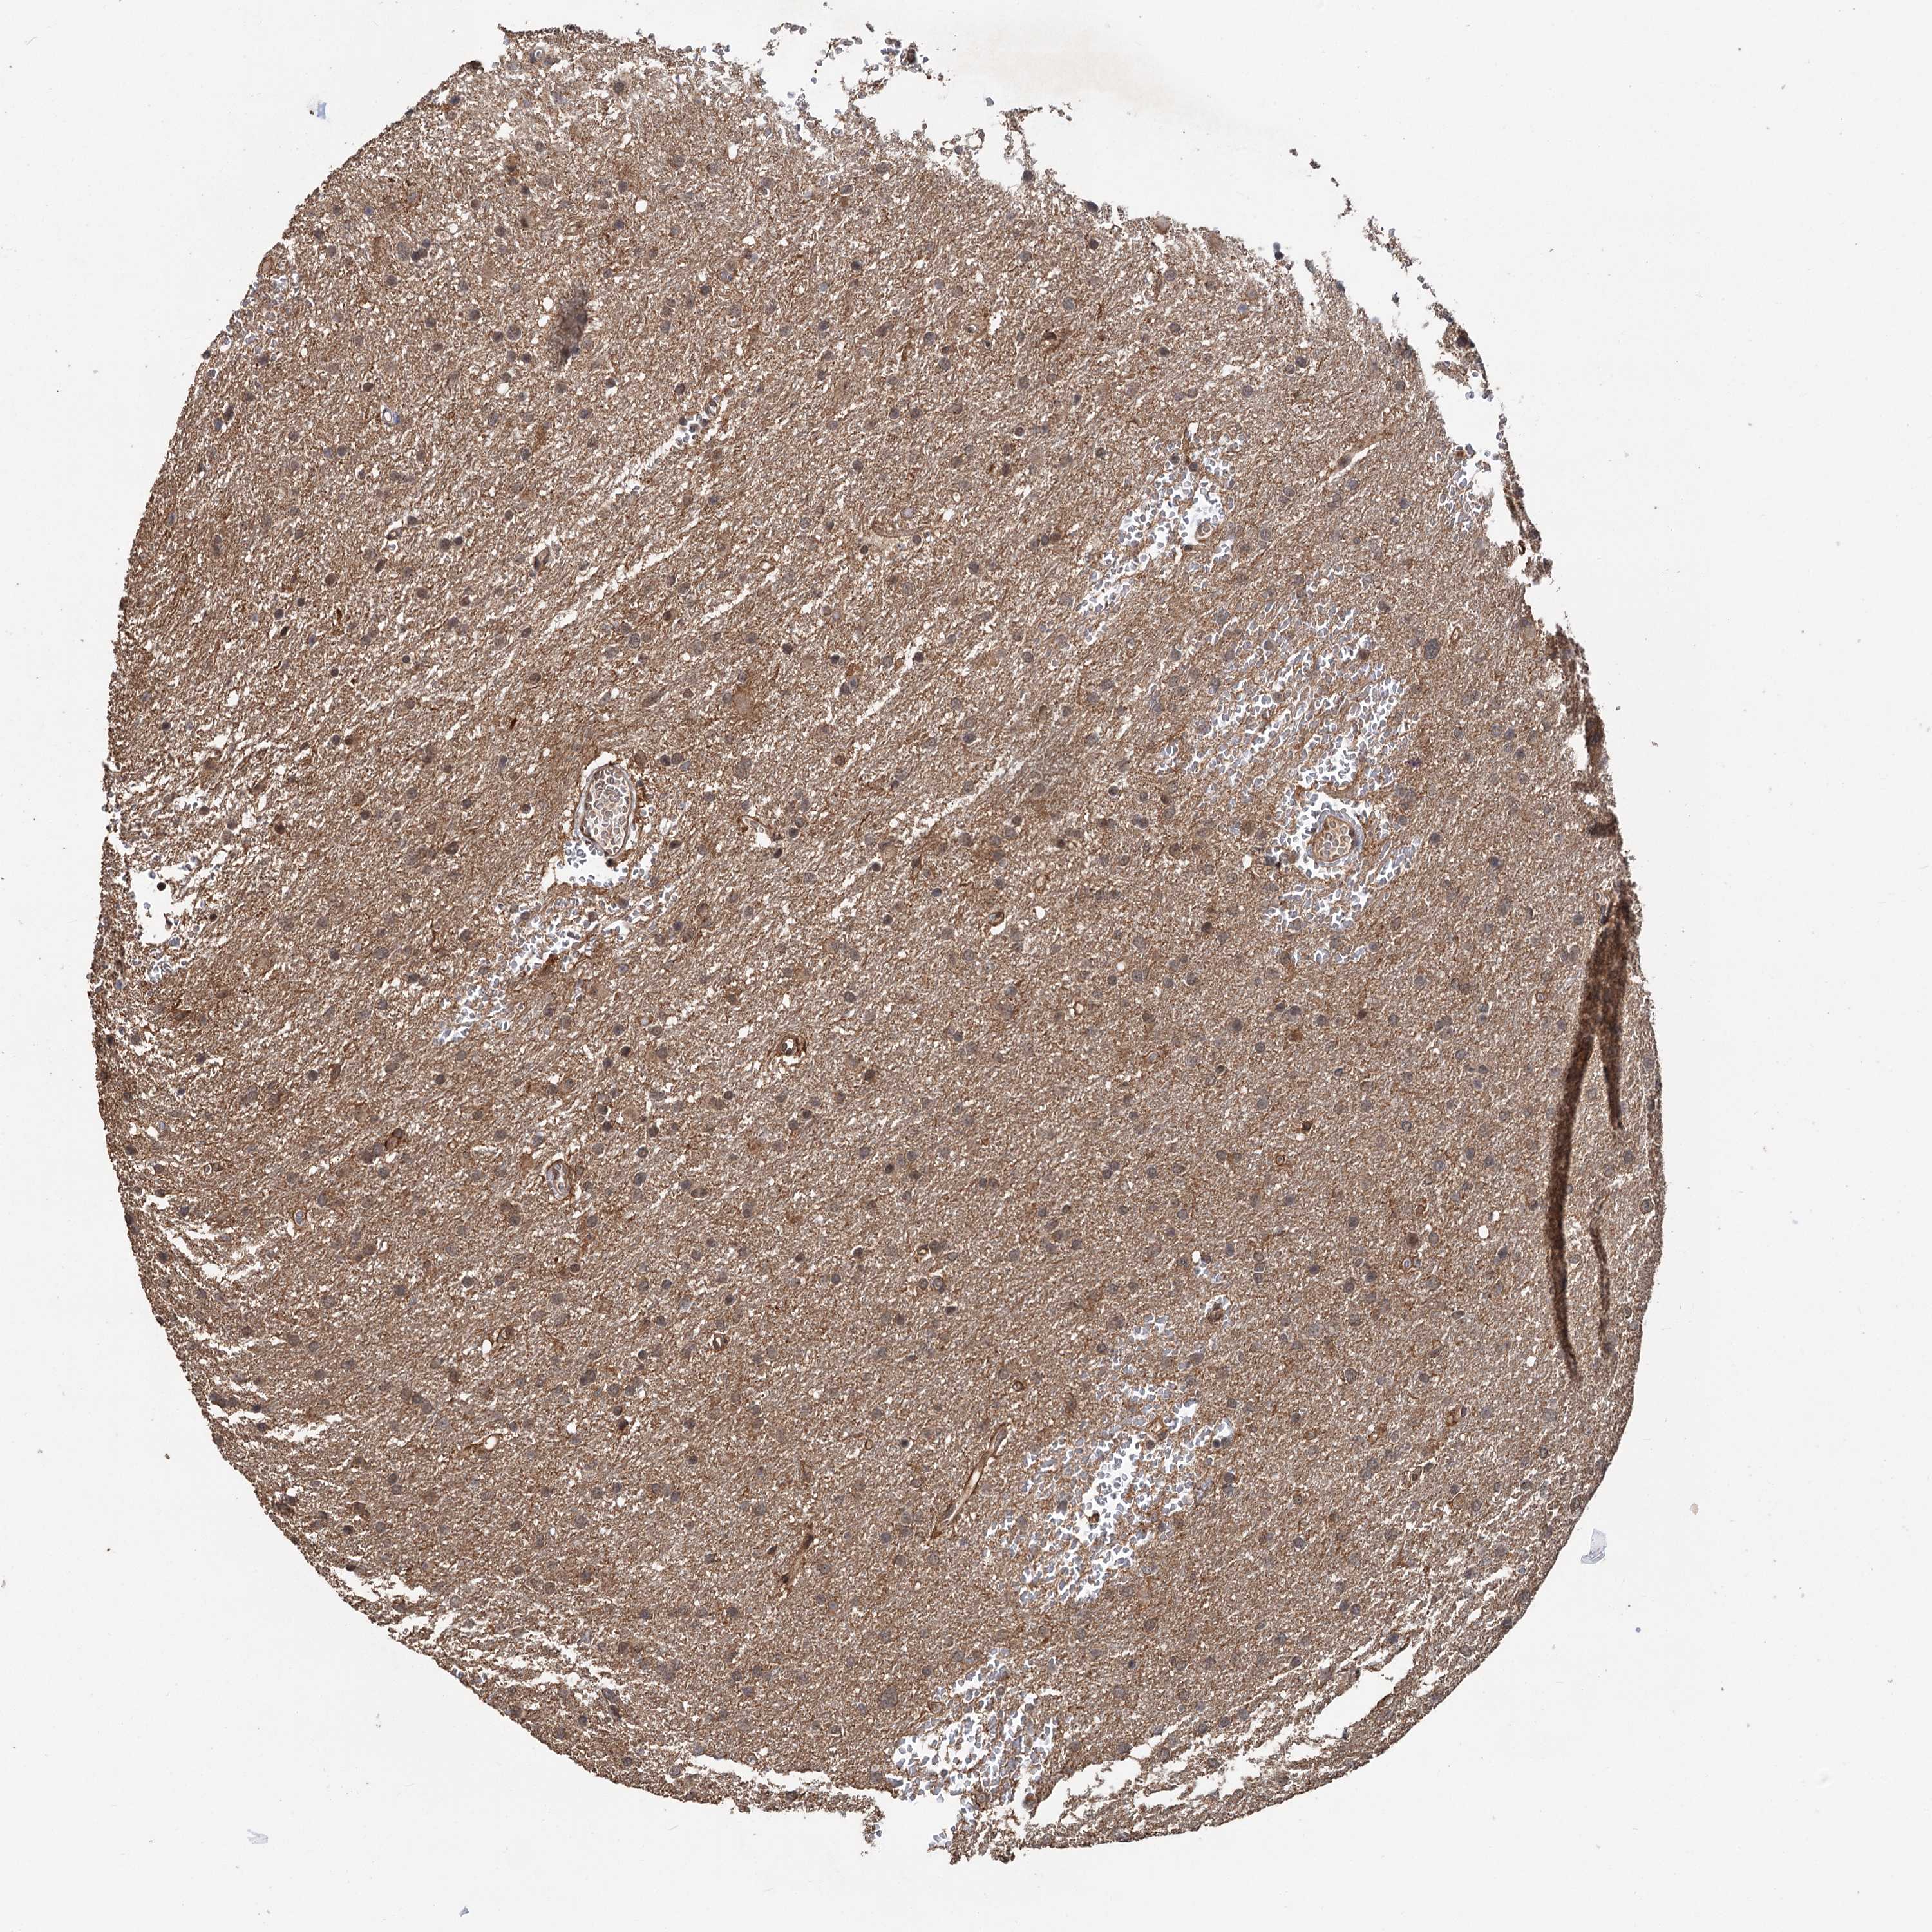

GLIOMA - Protein expressioni

A mouse-over function shows sample information and annotation data. Click on an image to view it in a full screen mode. Samples can be filtered based on level of antibody staining by selecting one or several of the following categories: high, medium, low and not detected. The assay and annotation is described here.

Note that samples used for immunohistochemistry by the Human Protein Atlas do not correspond to samples in the TCGA dataset.

Antibody stainingi

Antibody staining in the annotated cell types in the current human tissue is reported as not detected, low, medium, or high, based on conventional immunohistochemistry profiling in selected tissues. This score is based on the combination of the staining intensity and fraction of stained cells.

Each image is clickable and will lead to virtual microscopy that enables deeper exploration of all samples and also displays staining intensity scores, fraction scores and subcellular localization as well as patient and tissue information for each sample.

Antibody HPA038497

Antibody HPA038498

Staining

High

Medium

Low

Not detected

Intensity

Strong

Moderate

Weak

Negative

Quantity

>75%

75%-25%

<25%

None

Location

Nuclear

Cytoplasmic/membranous

Cytoplasmic/membranous,nuclear

Glioma, malignant, High grade

Glioma, malignant, Low grade